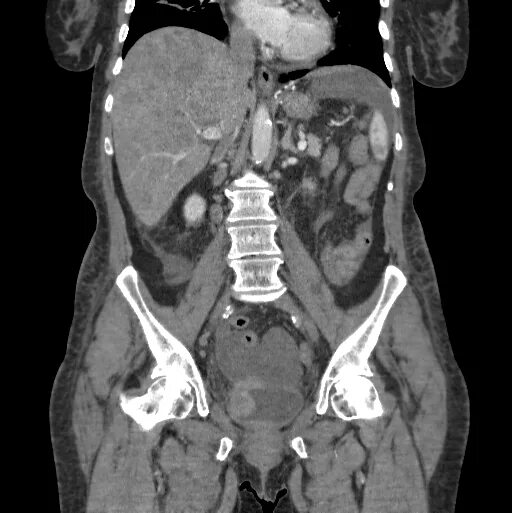

Таза абдоминально